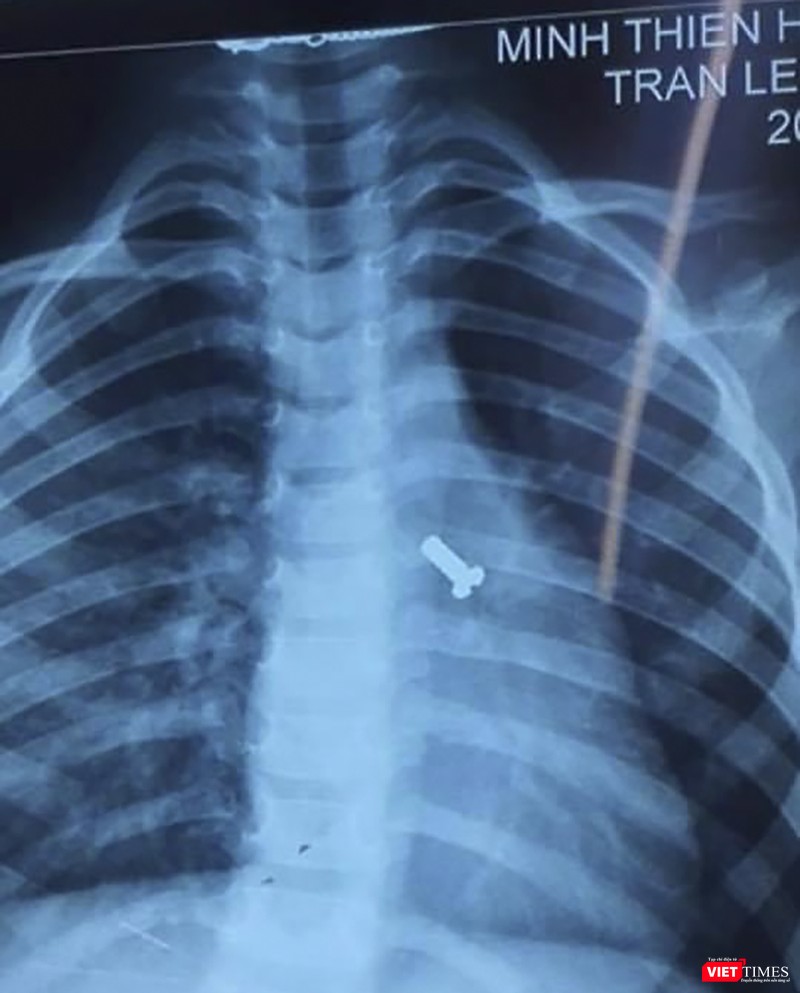

“Bệnh nhân N. nhập viện trong tình trạng khó thở đột ngột, cơ thể tím tái không rõ nguyên nhân nên gia đình đã đưa vào bệnh viện cấp cứu. Qua thăm khám và chụp X-quang, chúng tôi đã phát hiện một ốc vít nằm ở đường thở của trẻ” - bác sĩ CKII. Lê Mạnh Hoàng-Trưởng khoa Mắt-Tai Mũi Họng-Răng Hàm Mặt (Bệnh viện Phụ sản - Nhi Đà Nẵng) - cho biết.

Phim X-quang đinh vít nằm ở đường thở của trẻ

Theo bác sĩ CKII Lê Mạnh Hoàng, đây là trường hợp cấp cứu, cần can thiệp tức thì nên ê kíp bác sĩ nhanh chóng đưa bệnh nhi vào phòng mổ. Quá trình nội soi và lấy ốc vít ra khỏi đường thở thành công, không để lại tổn thương cho trẻ. “Rất may ca bệnh được phát hiện sớm, chẩn đoán và xử trí kịp thời chứ không hậu quả thật khó lường” – bác sĩ Hoàng chia sẻ.